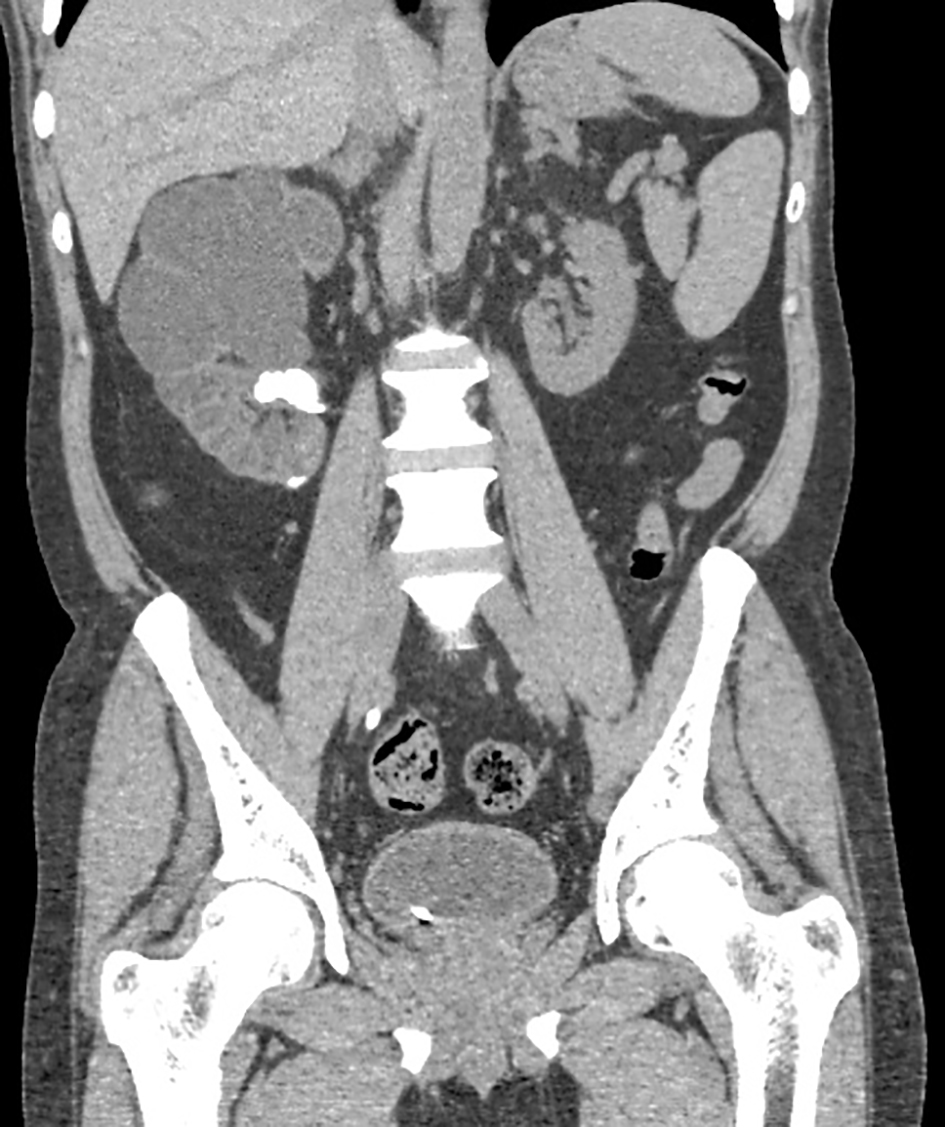

![]() Click for large image | Figure 1. Coronal NCCT image showing gross hydronephrosis involving the right kidney with calculus in the lower major calyx and gross parenchymal thinning. Ureteric stent is also noted on the right side. |

Antibiotic susceptibility testing done and interpreted following CLSI guidelines [3] showed strain was sensitive to ceftriaxone and cefexime and resistant to ampicillin, nalidixic acid, cotrimoxazole and quinolones. Following the sensitivity report, antibiotic treatment was changed to cefixime 200 mg twice a day for 2 weeks and patient was advised to come for follow-up and evaluation of renal functions. Percutaneous nephrolithotomy (PCNL) was planned if the renal functions improved. On follow-up after 2 weeks, his serum urea level was 75 mg/dL (reference range 10 - 50 mg/dL), serum creatinine was 2.4 mg/dL (reference range 0.5 - 1.3 mg/dL) and urine R/M still showed pus cells full field. Abdomen USG showed right-sided hydronephrosis with renal calculus and left renal cyst. The same antibiotics were continued and his renal parameters were monitored. After 6 weeks, PCNL was performed and urine, stones and DJ cultures were sent to the microbiology laboratory. All the three revealed growth of Salmonella typhi with the same antibiotic susceptibility pattern as earlier. Thus, the treatment was continued for another 2 weeks.